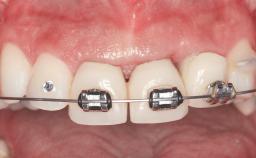

Replacement of Two Central Incisors with Non-Splinted Crowns on Bone-Level Implants

A 27-year-old female patient was referred to the Clinic of Oral Surgery and Stomatology of the University of Bern due to acute pain in the region of her two maxillary central incisors. The patient was in good general health. She reported a bicycle accident approximately 5 years earlier in which teeth 11 and 21 had been traumatized but neither fractured nor displaced. Several weeks after the accident, endodontic treatment was performed on both central incisors, although the patient did not recall the precise reasons for this decision. About 2 years ago, non-vital bleaching had been conducted, in accordance with the “walking-bleach” principle, due to progressive discoloration of teeth 11 and 21.